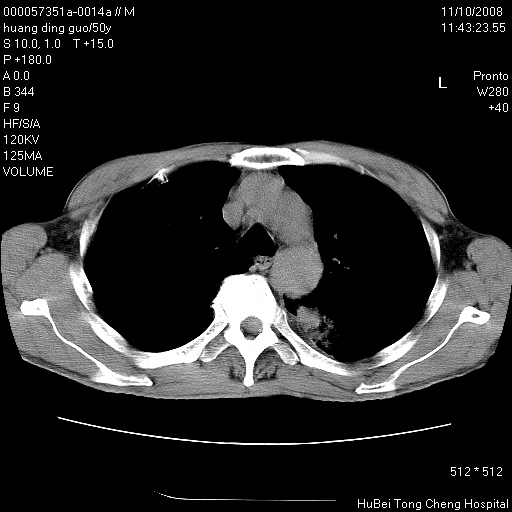

患者 男,50岁。左侧腰背部疼痛3月余,伴消瘦。平素健康,无传染病史。

胸部ct轴位平扫(层厚10mm,螺距1.5,重建间隔10mm),图像如下:

左肺下叶背段有一厚壁空洞,外壁呈锯齿状伴毛刺改变。空洞相邻胸膜有牵拉改变。左肺下叶血管支气管束不规则增粗,小叶间隔增厚。胸椎骨质破坏。考虑左肺下叶周围型肺癌伴左肺下叶癌性淋巴管炎、胸椎转移。

左肺下叶背段有一厚壁空洞,外壁呈锯齿状伴毛刺改变。空洞相邻胸膜有牵拉改变。左肺下叶血管支气管束不规则增粗,小叶间隔增厚。胸椎骨质破坏。考虑左肺下叶周围型肺癌伴阻塞性肺炎、胸椎转移。其他待排

左肺下叶背段有一厚壁空洞,内壁不规则,外壁呈锯齿状伴毛刺改变。空洞相邻胸膜有牵拉改变。周围呈絮状炎性改变,左肺下叶血管支气管束不规则增粗,小叶间隔增厚。胸椎骨质破坏。考虑左肺下叶周围型肺癌伴左肺下叶阻塞性肺炎、胸椎转移。